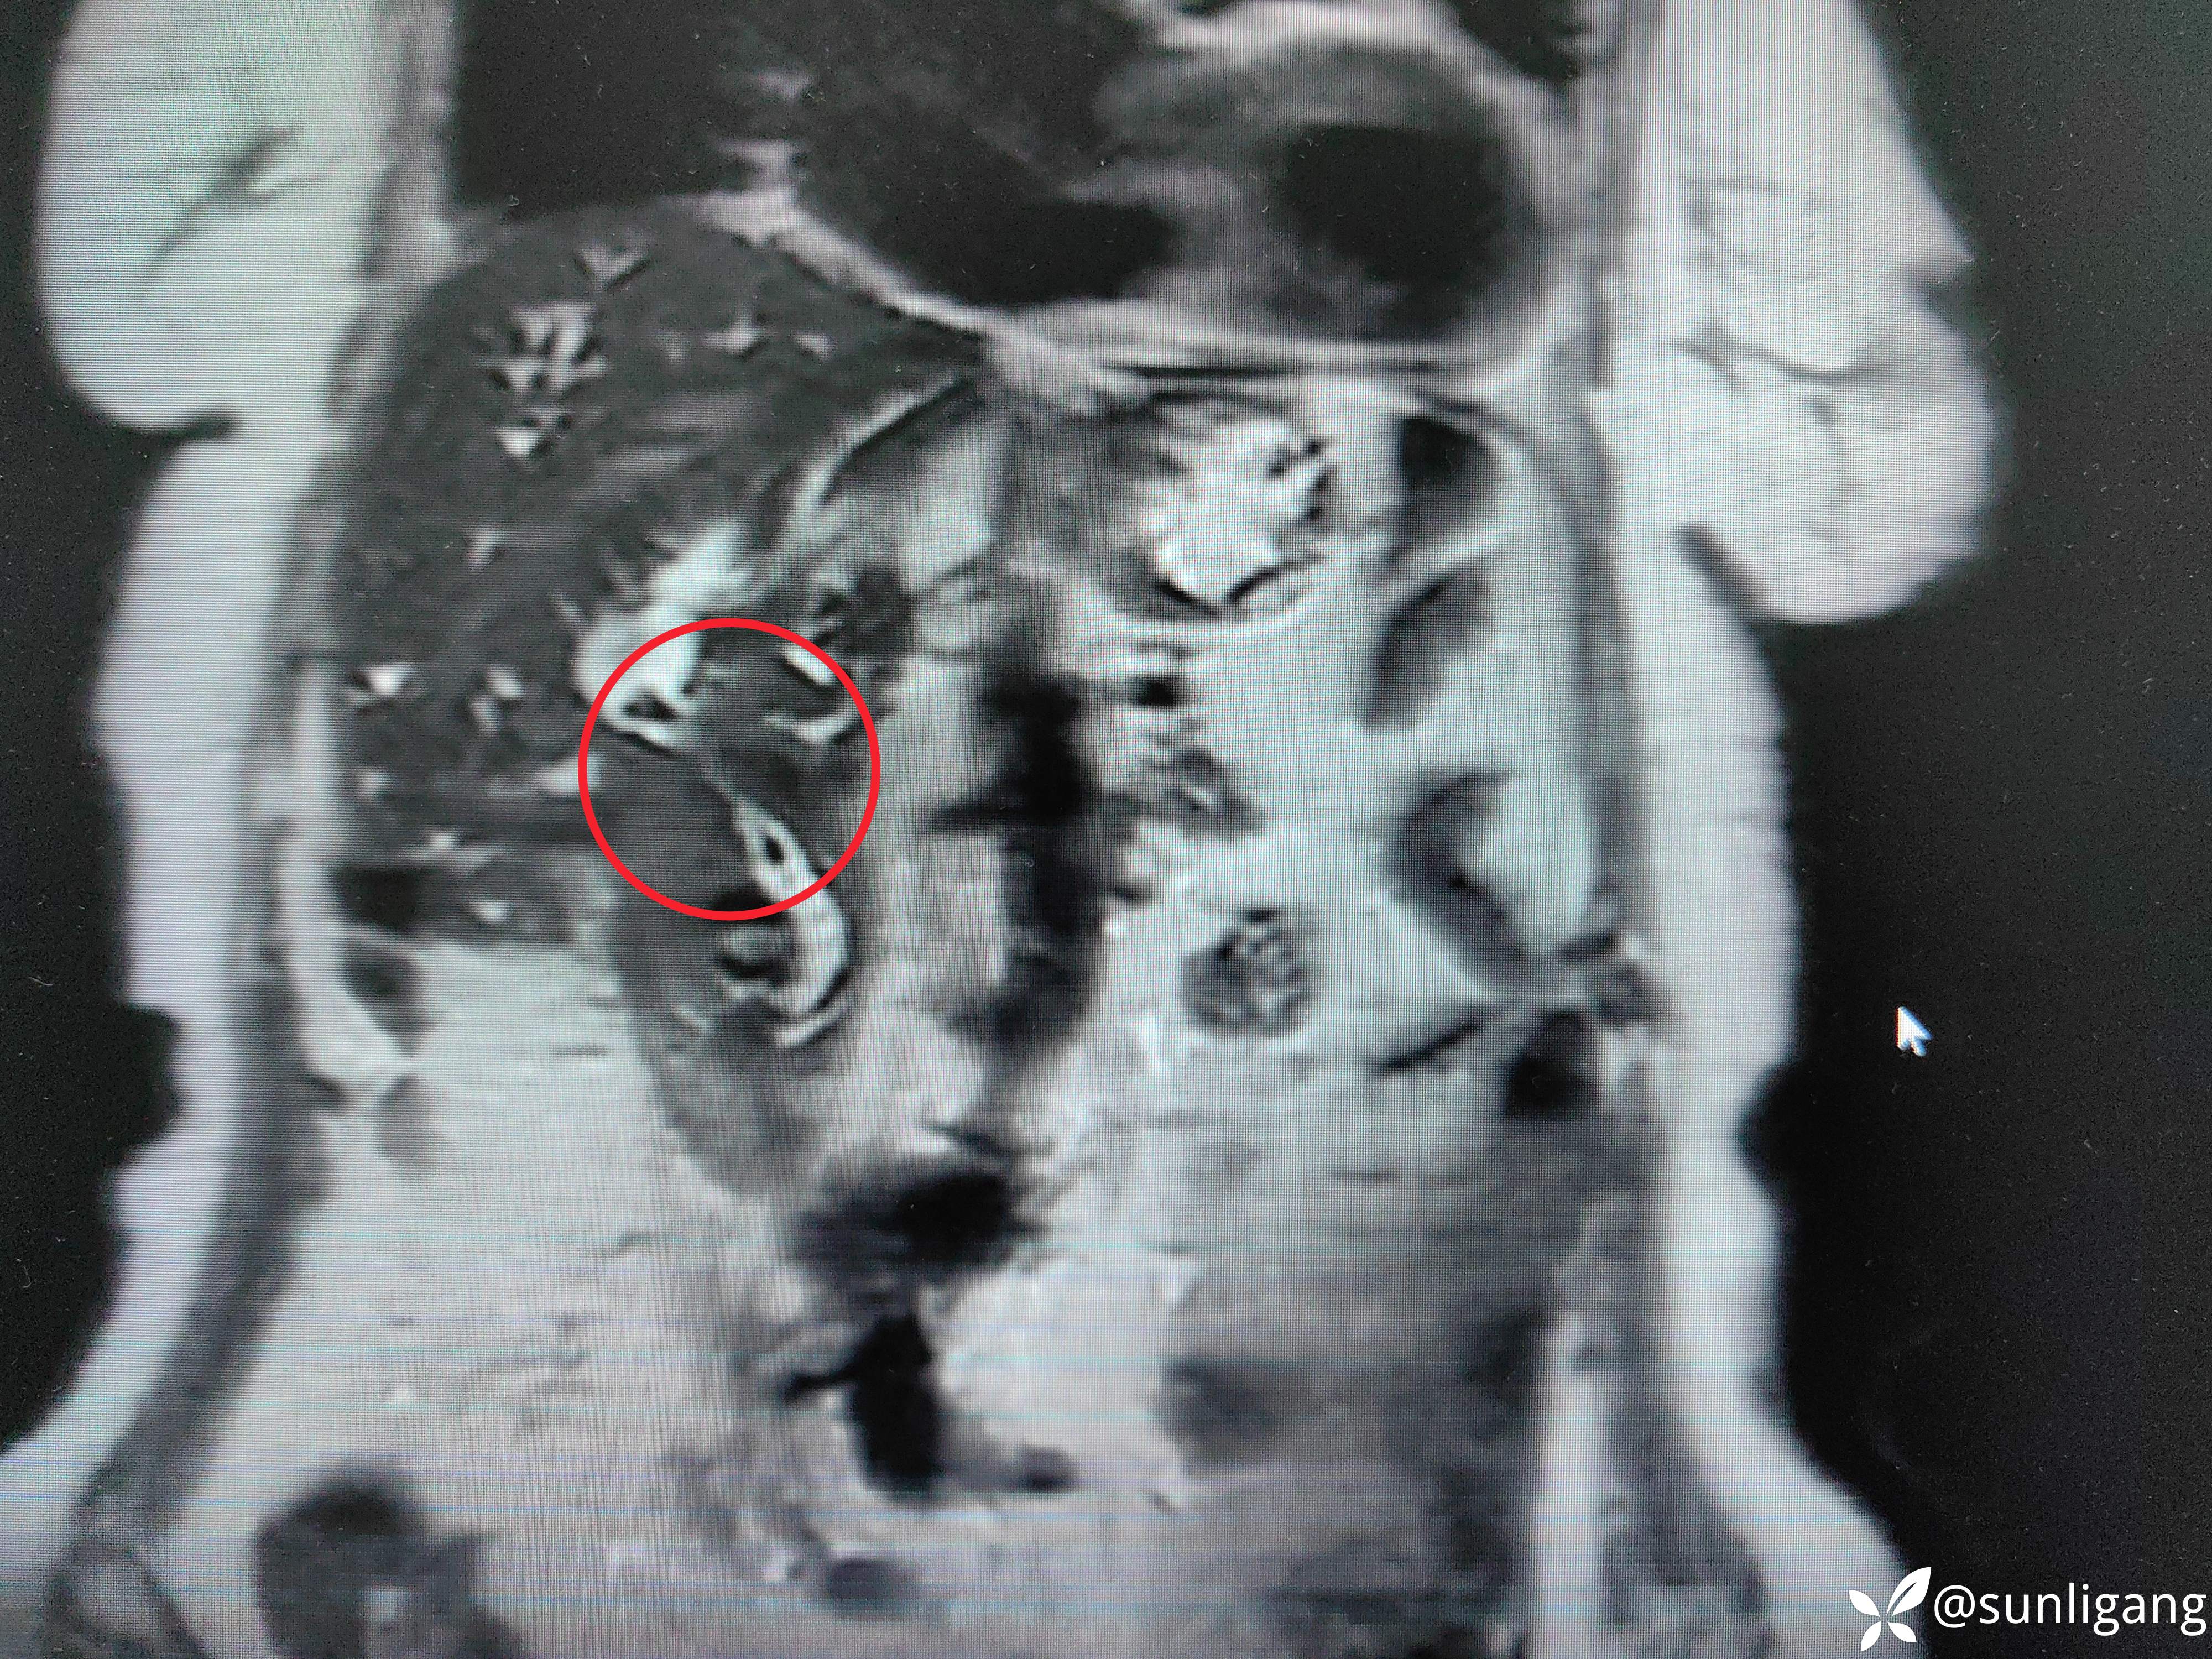

磁共振:

可见明显胆囊结石影

可见中断的中段胆管影以及扩张的肝总管、正常的胰管

可见明显变窄的胆总管(肿瘤直接侵犯?压迫?)